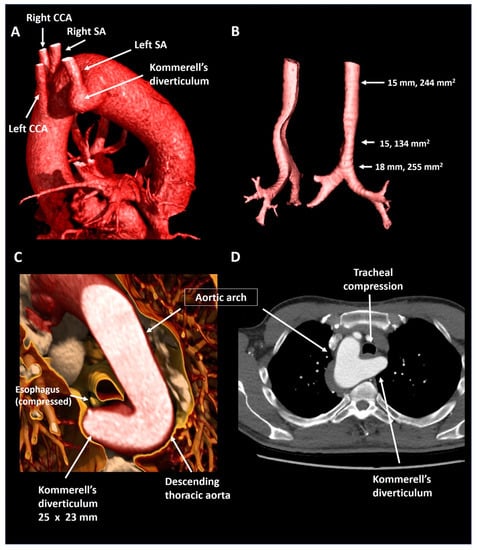

| Patient 3 | 50 | Female | Right-sided arch, aberrant LSA and KD | Symptomatic tracheal and esophageal compression | 30 × 29 mm, 870 mm2 | Dysphagia and dyspnea | Surgical resection |

| Patient 4 | 55 | Male | Right-sided arch, aberrant LSA and KD | Mild tracheal compression | 25 × 23 mm, 575 mm2 | Mild dyspnea, although excellent objective exercise capacity | Structural imaging follow-up |